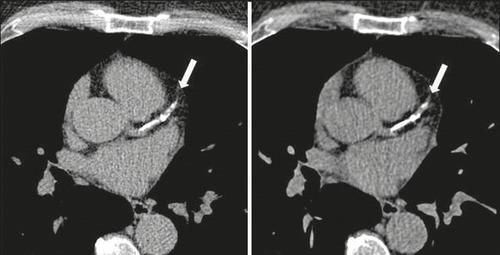

第四个要说的是“动脉钙化”,动脉钙化在人群当中也很常见。很多时候是在体检报告的胸部X光片或CT扫描结果里,可以看到“主动脉钙化”、“冠脉钙化”等提示。

钙化的本质是钙质在血管壁内的沉积,这被认为是动脉硬化的明确信号,同时也是血管老化的表现。